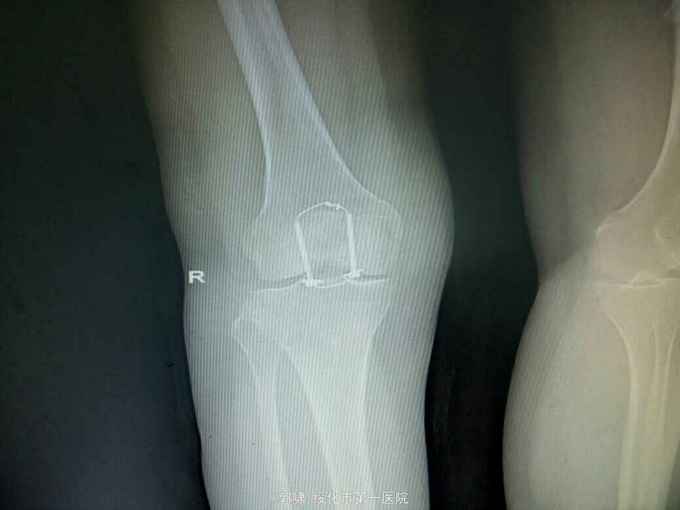

左膝关节摔伤,肿胀,畸形,活动受限一小时。收入院。患者于一小时前滑倒摔伤。当即倒地,左膝关节肿胀,畸形不能行走。门诊拍片示:左膝关节髌骨骨折,断端移位。门诊以左髌骨骨折收入院。

左膝关节肿胀,局部畸形,不能下地行走。浮髌试验阳性。拍片示:左髌骨骨折。

诊断:左髌骨骨折。立即予以腰麻下行切开复位内固定术。术中复位骨折,缝合筋膜,冰水浸泡髌骨爪约10分钟。待髌骨爪变软。选取合适大小的髌骨爪。应用记忆合金髌骨爪内固定。立即用40°温盐水热敷局部。使记忆合金加速抓紧。环抱。缝合爪齿二道,防止脱落。缝合关节囊,韧带组织。术毕。

应用记忆合金髌骨爪内固定髌骨骨折。手术时间基本在20----30分钟内都可以完成。局部损伤小。固定牢靠,确实。患者二个月就可以下地负重活动。具体手术技巧。一是髌骨爪提前用冰盐水侵泡10分钟左右。待记忆合金变软即可使用。二。固定牢靠后立即用40°温盐水热敷。使其快速抓紧。三,缝合爪齿,防脱。四如有粉碎,小的骨块可以缝合筋膜固定。有大骨块,最好环扎钢丝,或穿针固定,有时穿骨隧道钢丝捆扎。效果也不错。只要做到以上几点。安全无忧了!以下是以前做的片子。可以看一看。